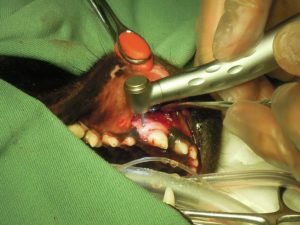

5.折れた歯を抜いて、周囲の骨をきれいにしてから

6.縫合をします。